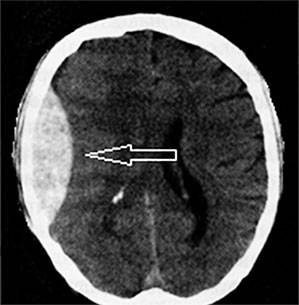

- неврологическими симптомами (сонливостью, нарушением сознания, головными болями, головокружениями), что может быть принято за симптомы микроинсульта или инсульта головного мозга;

Если больной переживает последствия инсульта, то на первый план может выйти спутанность сознания и дыхательные расстройства.